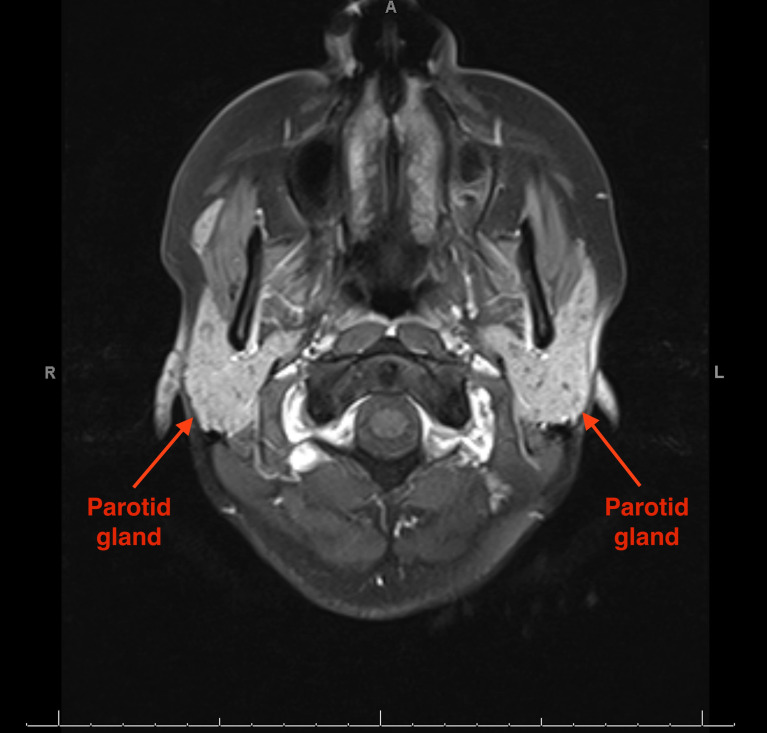

Salt and Pepper Parotid Changes in Sjögren's Syndrome.

盐和胡椒在Sjögren综合征中的腮腺变化。